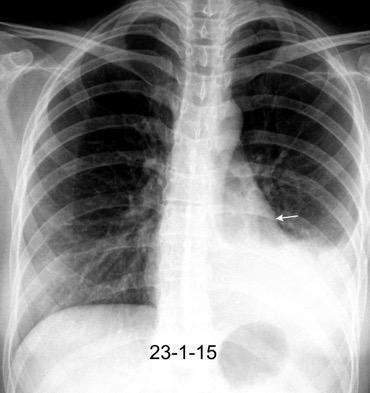

En relación con trasudados tabicados. Insuficiencia cardiaca

Hipoalbuminemia

Cirrosis / Fallo renal.

Operado aneurisma (prótesis). Líquido tabicado en cisuras

Fernandes de Paula MC et al. Focal pleural tumorlike conditions: Nodules and masses beyond mesotheliomas and metastasis. Respiratory Medicine 2015.

Derrame pleural “encapsulado”

“Tumor fantasma”

Asociado a fallo cardiaco. ( “Pleuritis adhesiva”). Buch KP. Chest. 2000